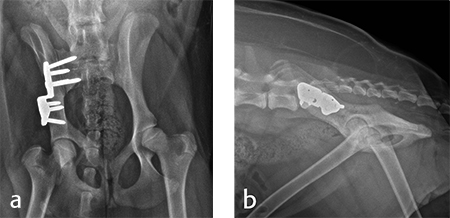

Postoperative radiographs revealed reduction in subluxation with capture of the femoral head in the right coxofemoral joint (Fig 4). Palpation of the hip revealed good stability of the right hip. Activity was restricted to leash walk only for 6 weeks postoperatively. Radiographic examination 7 weeks following surgery revealed healing of the ilial osteotomy, stable implants, and excellent coxofemoral conformation and stability (Fig 5).

Radiographic examination at 6 months postsurgery revealed stable implants, excellent coxofemoral conformation, and no evidence of osteoarthritis of the right hip. The left acetabulum was mildly shallow and mild subluxation of the femoral head was present at follow-up examination (Fig 6). Early osteophytosis in the region of the left femoral neck was evident. The dog was using the right hind leg normally and was showing no signs of instability or pain of the right hip. Mild instability and pain of the left hip was present on palpation. The dogs left hip was treated with a joint supplement and NSAIDs as needed. Future THR will be performed if clinical signs no longer respond to medical treatment.